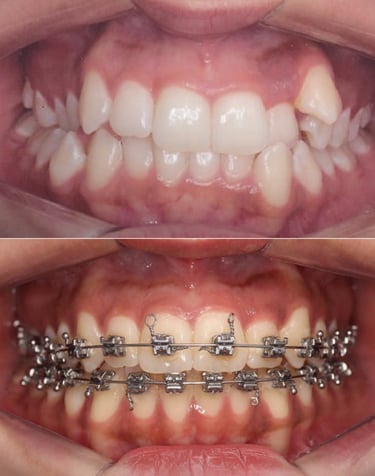

EVOLUÇÃO